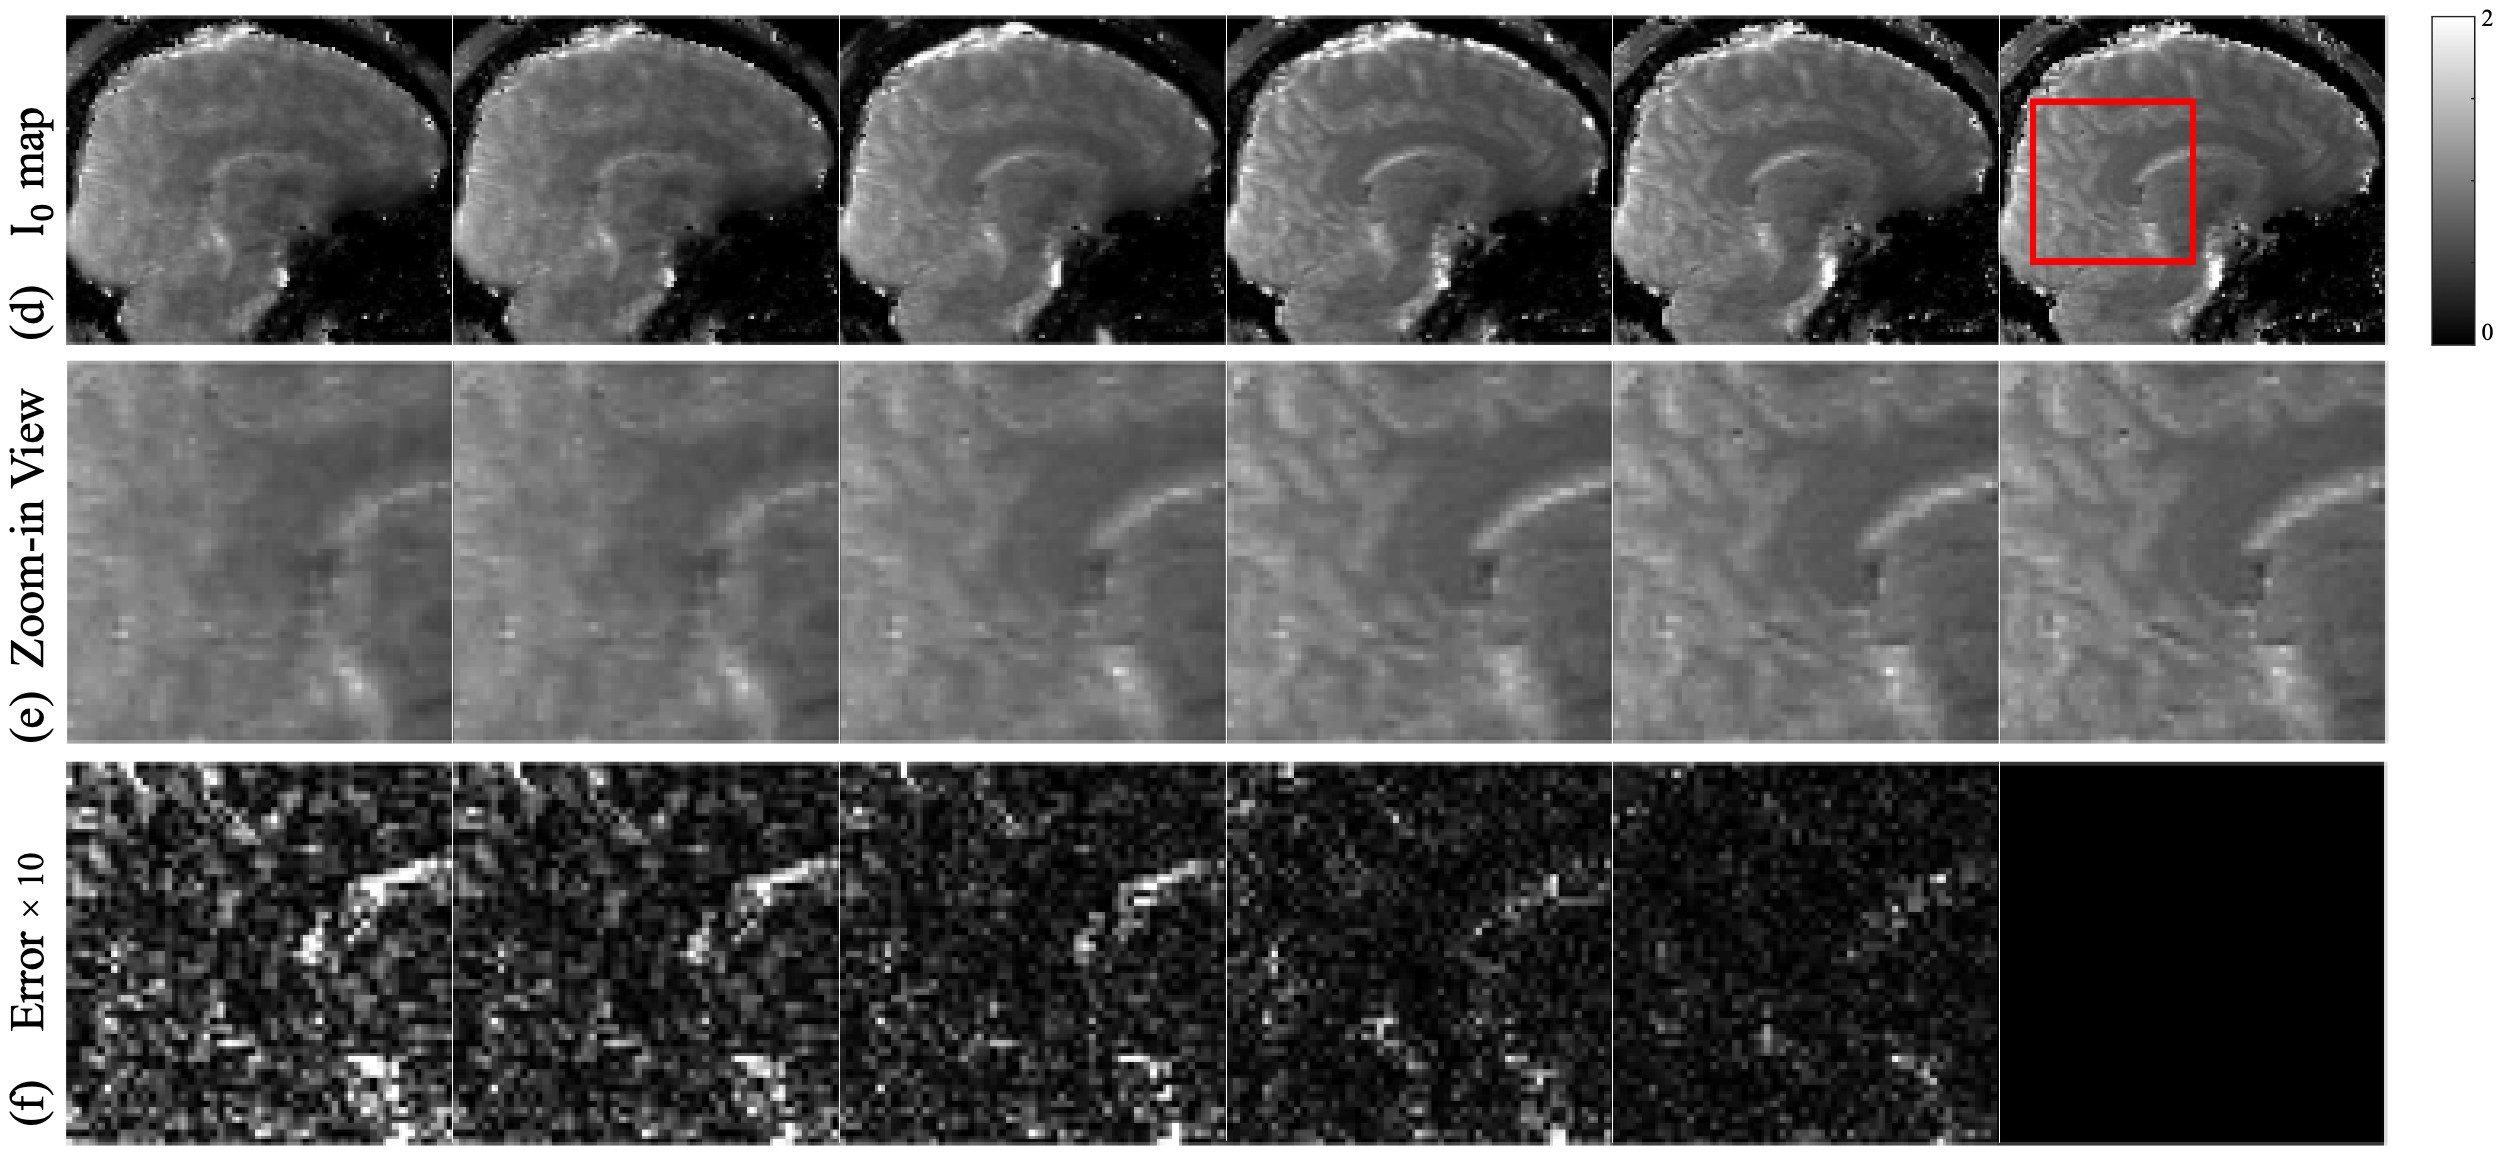

The maps in Fig 5(d-f) exhibit a similar signature in reconstruction quality as the maps, where LLR and Model-TGV show aliasing artifacts with the most blur, further confirmed by the zoom-ins, reflecting the undersampling pattern of many high frequency data points being undersampled with low frequency data points fully sampled. The deep learning method RELAX shows its ability to denoise through artifacts removal and detail preservation. However, it still lacks sharpness resulting in smoothened edges. Quantitative DiMo produces the sharpest maps preserving detail, which again is confirmed by its error maps, showing least error.